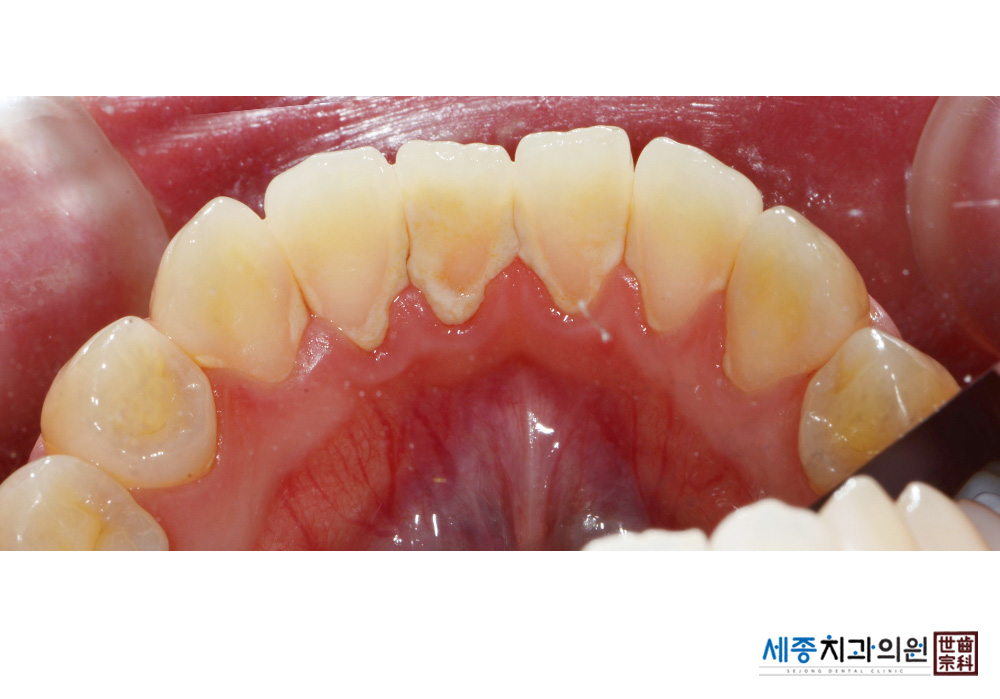

[스케일링] 치주질환 예방 스케일링

치료전 : 2020-03-02

가글마취&저주파 스켈러를 사용한 스케일링